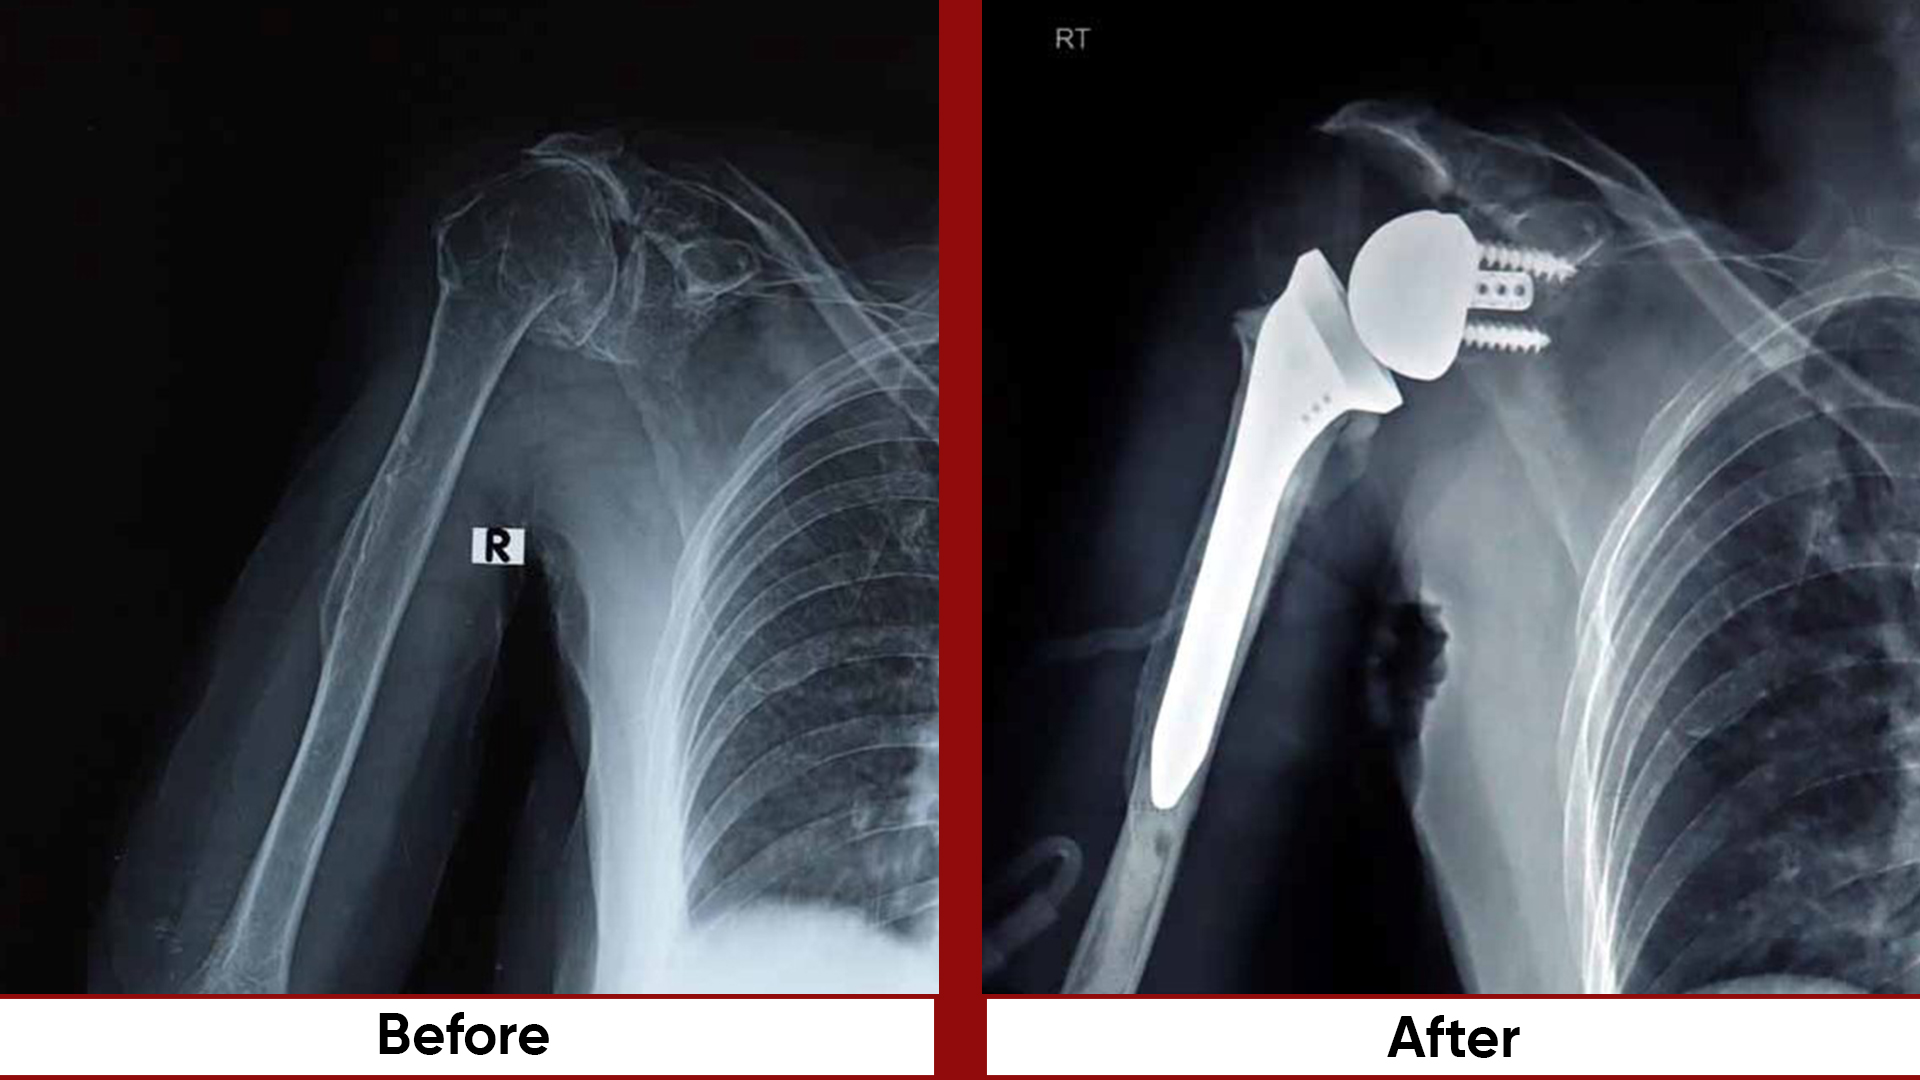

Procedures

• Total Hip Replacement (THR)

• Arthroscopic Surgeries (Knee & Shoulder)

• Bone Tumor Management